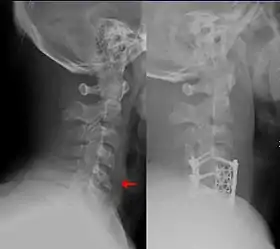

| Teardrop fracture of the cervical spine before and after treatment with metal fixation | |

A flexion teardrop fracture is a fracture of the anteroinferior aspect of a cervical vertebral body due to flexion of the spine along with vertical axial compression.[1] The fracture continues sagittally through the vertebral body, and is associated with deformity of the body and subluxation or dislocation of the facet joints at the injured level.[2] A flexion teardrop fracture is usually associated with a spinal cord injury, often a result of displacement of the posterior portion of the vertebral body into the spinal canal.[3]

The flexion teardrop fracture should not be confused with a similar-looking vertebral fracture called "extension teardrop fracture". Both usually occur in the cervical spine, but as their names suggest, they result from different mechanisms (flexion-compression vs. hyperextension). Both are associated with a small fragment being broken apart from the anteroinferior corner of the affected vertebra. Flexion teardrop fractures usually involve instability in all elements of the spine at the injured level, commonly occur at the C4-C7 vertebra, and have a high association with spinal cord injury (in particular anterior cord syndrome). In comparison, the extension-type fracture occurs more commonly at C2 or C3, causes less if any disruption to the middle and posterior elements, and does not usually result in spinal cord injury (however it may co-occur with more dangerous spine injuries).[4][5]